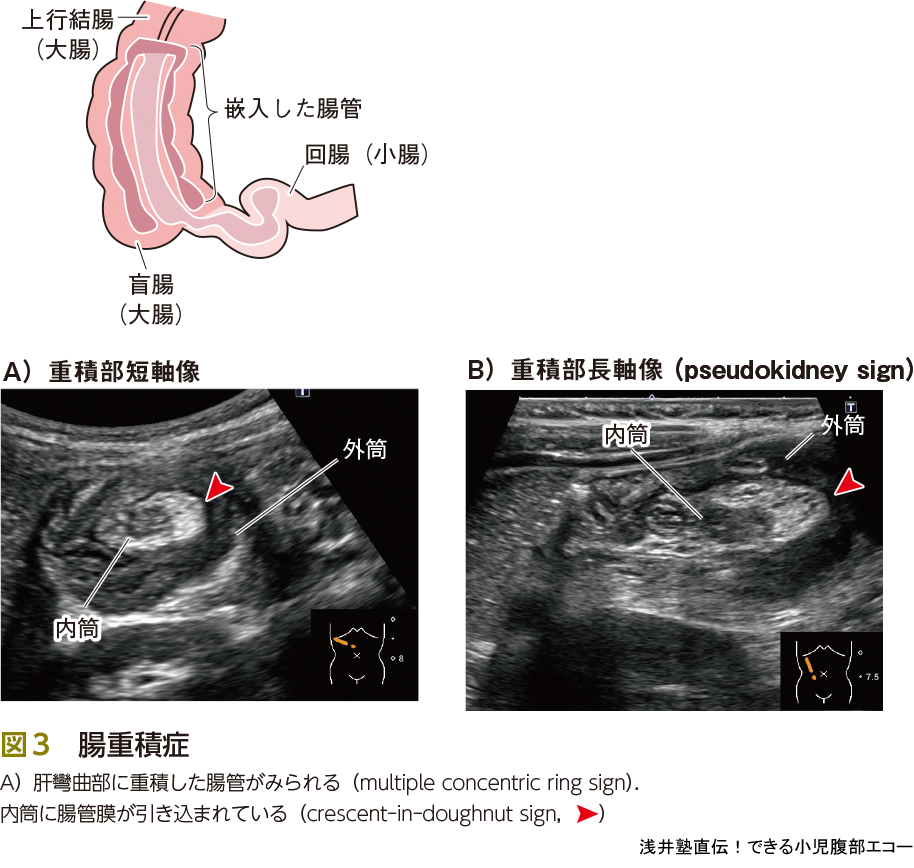

腸重積症は口側の腸管が肛門側の腸管に嵌入する小児の重要な危急疾患です.重積が最も多くみられる部位は,肝彎曲部です(図3).重積した腸管の短軸像はmultiple concentricring signと表現されます.その外筒と内筒の間に腸間膜が引き込まれている状態はcrescent in doughnut signとよばれ,重要な所見です.また,短軸像だけでは見落とすこともありますので長軸像でも確認することが大事です.長軸像は腎臓に似ていることからpseudokidney signとよびます(図3B).